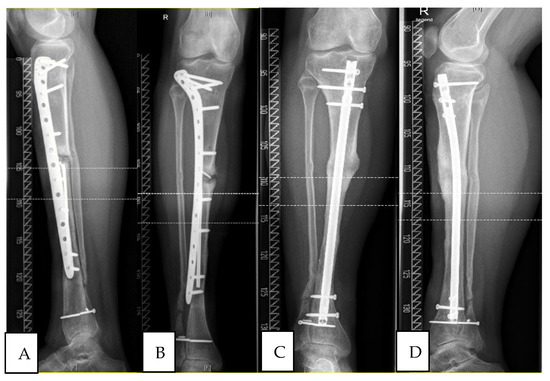

Clinical Observations of the Effectiveness of the Masquelet Induced Membrane Technique in the Treatment of Critical Long-Bone Defects of the Lower and Upper Extremities

by Kamil Kołodziejczyk, Aleksander Ropielewski, Rafał Garlewicz, Marcin Złotorowicz and Jarosław Czubak

Medicina 2024, 60(12), 1933; https://doi.org/10.3390/medicina60121933 - 24 Nov 2024

Background and Objectives: Successful treatment of severe trauma and fractures of the long bones with successful healing and bone union is still a significant challenge for surgeons. Unfortunately, up to 10% of long-bone fractures develop bone healing disorders. The aim of this study was to evaluate the results of treating bone defects with different etiologies in the upper and lower extremities using the induced membrane technique. Materials and Methods: We prospectively evaluated the radiological and clinical outcomes of 45 patients with severe bone defects treated with the induced membrane technique during the period from May 2021 to October 2023. The time to bone defect regeneration, size of the bone defect, and the cost of treatment were evaluated. Functional outcomes were assessed using the Disabilities of the Arm Shoulder and Hand (DASH) scale, SF-36, and the Lower Limb Functional Index (LLFI). Results: The mean follow-up time was 31 months (12–35). There were 20 patients with upper extremity bone defects and 25 with lower extremity bone defects. The mean defect length was 7.9 cm for the upper extremity (3.5–18) and 5.3 cm for the lower extremity (3–11). The mean times to achieve bone union and remodeling were 6.0 months (3–12) and 9 months (3–13) for the upper and lower limbs, respectively. Clinical evaluation at the end of treatment (achieving bone union) showed statistically significant improvements in the DASH, SF-36, and LLFI scales for pre- and postoperative outcomes. There was no statistical significance in the SF-36 clinical scale scores after surgical treatment compared to reconstructive treatment of upper and lower extremity bone defects. Results: The presented reconstructive approach to the treatment of bone defects and healing disorders and extensive analysis demonstrate the effectiveness of the induced membrane technique in a short follow-up period, with a relatively high level of patient comfort and good clinical results in the treatment of severe bone defects with particularly infectious etiologies. Full article